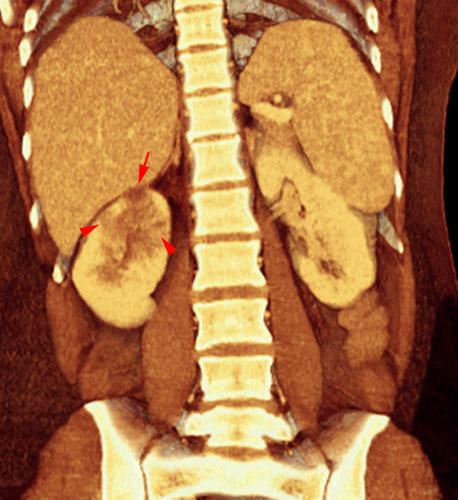

Pielonefritis aguda 2

VR seccional. Visión coronal anterior. TC contrastado en fase venosa poniendo de manifiesto múltiples focos hipodensos (puntas de flecha) que traducen una pielonefritis multifocal, con tendencia a la abscesificación de alguno de ellos (flecha)